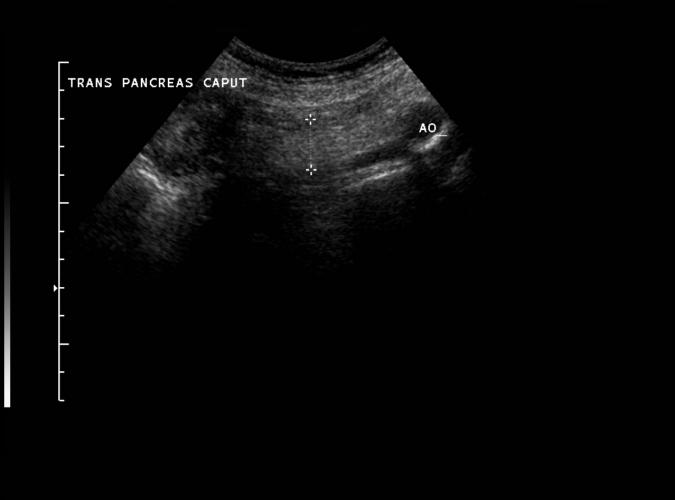

Standard bild.

Trans.caput pancreatis kranialt om och i anslutning till

pars horisontalis duodeni.